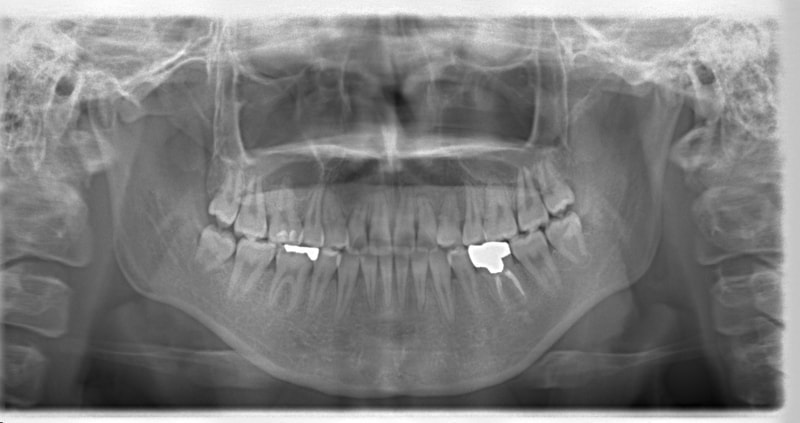

先天欠如歯両側上顎3番

治療法:フルパッシブブラケット:T21

治療開始時